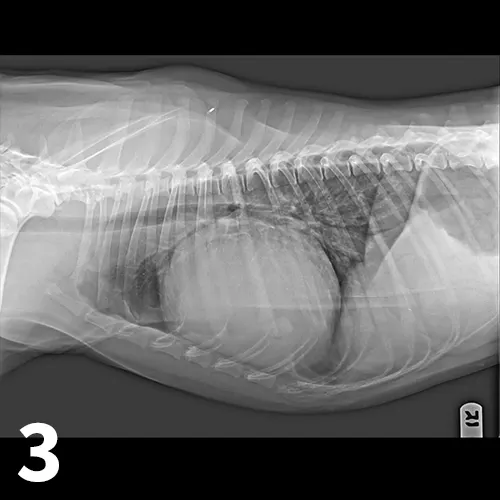

• Right atrial masses are most typically hemangiosarcoma (Figure 4).7

Featured Image

Figure 4

Right parasternal long-axis echocardiographic view of a dog with a small accumulation of pericardial effusion and an infiltrative right atrial mass (hemangiosarcoma most likely). (PE = pericardial effusion, RA = right atrium, LA = left atrium, LV = left ventricle)